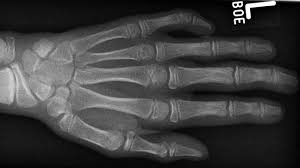

Having a crroked pinky means you, most likely need medical treatment. It's easy to take the humble pinkie for granted. When i bend my right arm i get. Curved pinky fingers usually indicate a fear of confrontation. I had a small cut which developed blisters. What does a curved pinky finger mean? Clinodactyly is a minor congenital malformation (birth defect). Two rings on the left pinky finger once indicated that a man was married. On the pinkie, it can show an early history of family problems. What causes clinodactyly & how is it treated? She said it's hereditary but neither my husband or i have them. What does the pinky finger do? The poor thing slammed the car door on his little pinky.

Usually only found on the index or little finger.